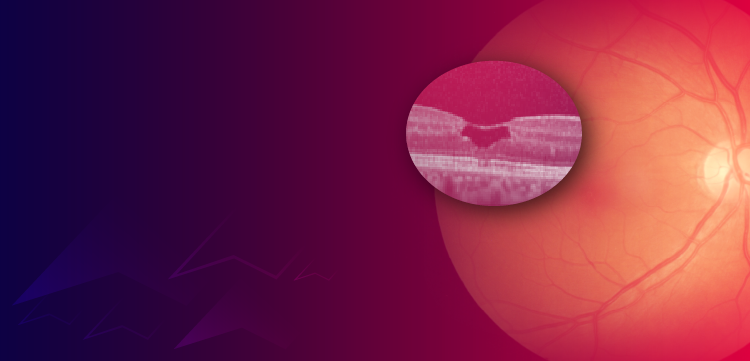

FIGURE 3

A lumbar spine image with T2 turbo spin-echo spectral adiabatic inversion recovery sequences is shown here.